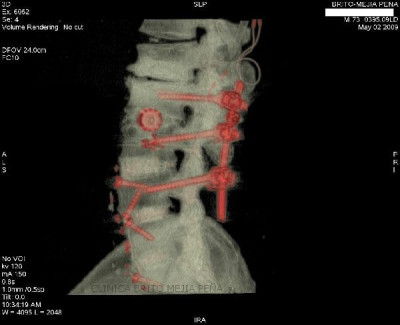

Instrumentalización columna 3D